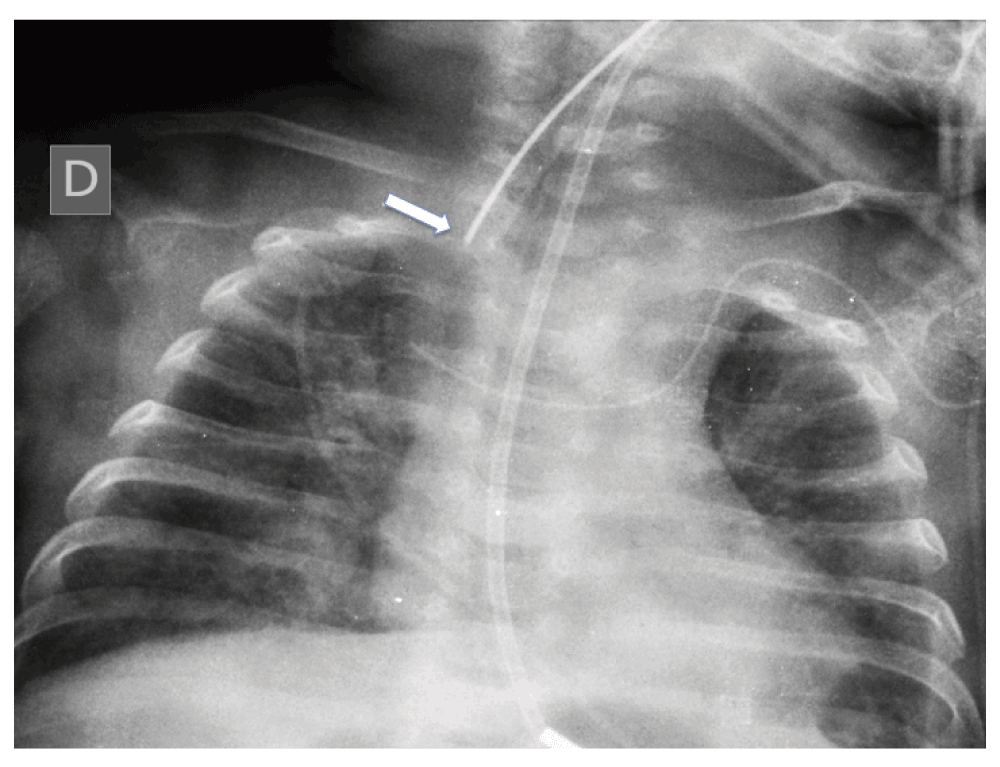

He was admitted to our pediatric intensive care unit 25 days after he had been discharged from the other hospital, and was immediately intubated. An X-ray showed a small amount of interstitial infiltrate, compatible with aspiration pneumonia. However, the respiratory distress was attributed mainly to an upper airway obstruction. It was difficult to tracheally intubate the infant; only an uncuffed 2.5 mm endotracheal tube (ETT) was able to be inserted into the trachea and it was difficult to place this in the right position. The X-ray after intubation showed the ETT in a high position and the trachea displaced to the right (Figure 2). Magnetic resonance imaging (MRI) revealed the extent of the cervical mass and its compression on the trachea, and the latter’s subsequent displacement (Figure 3a and 3b).